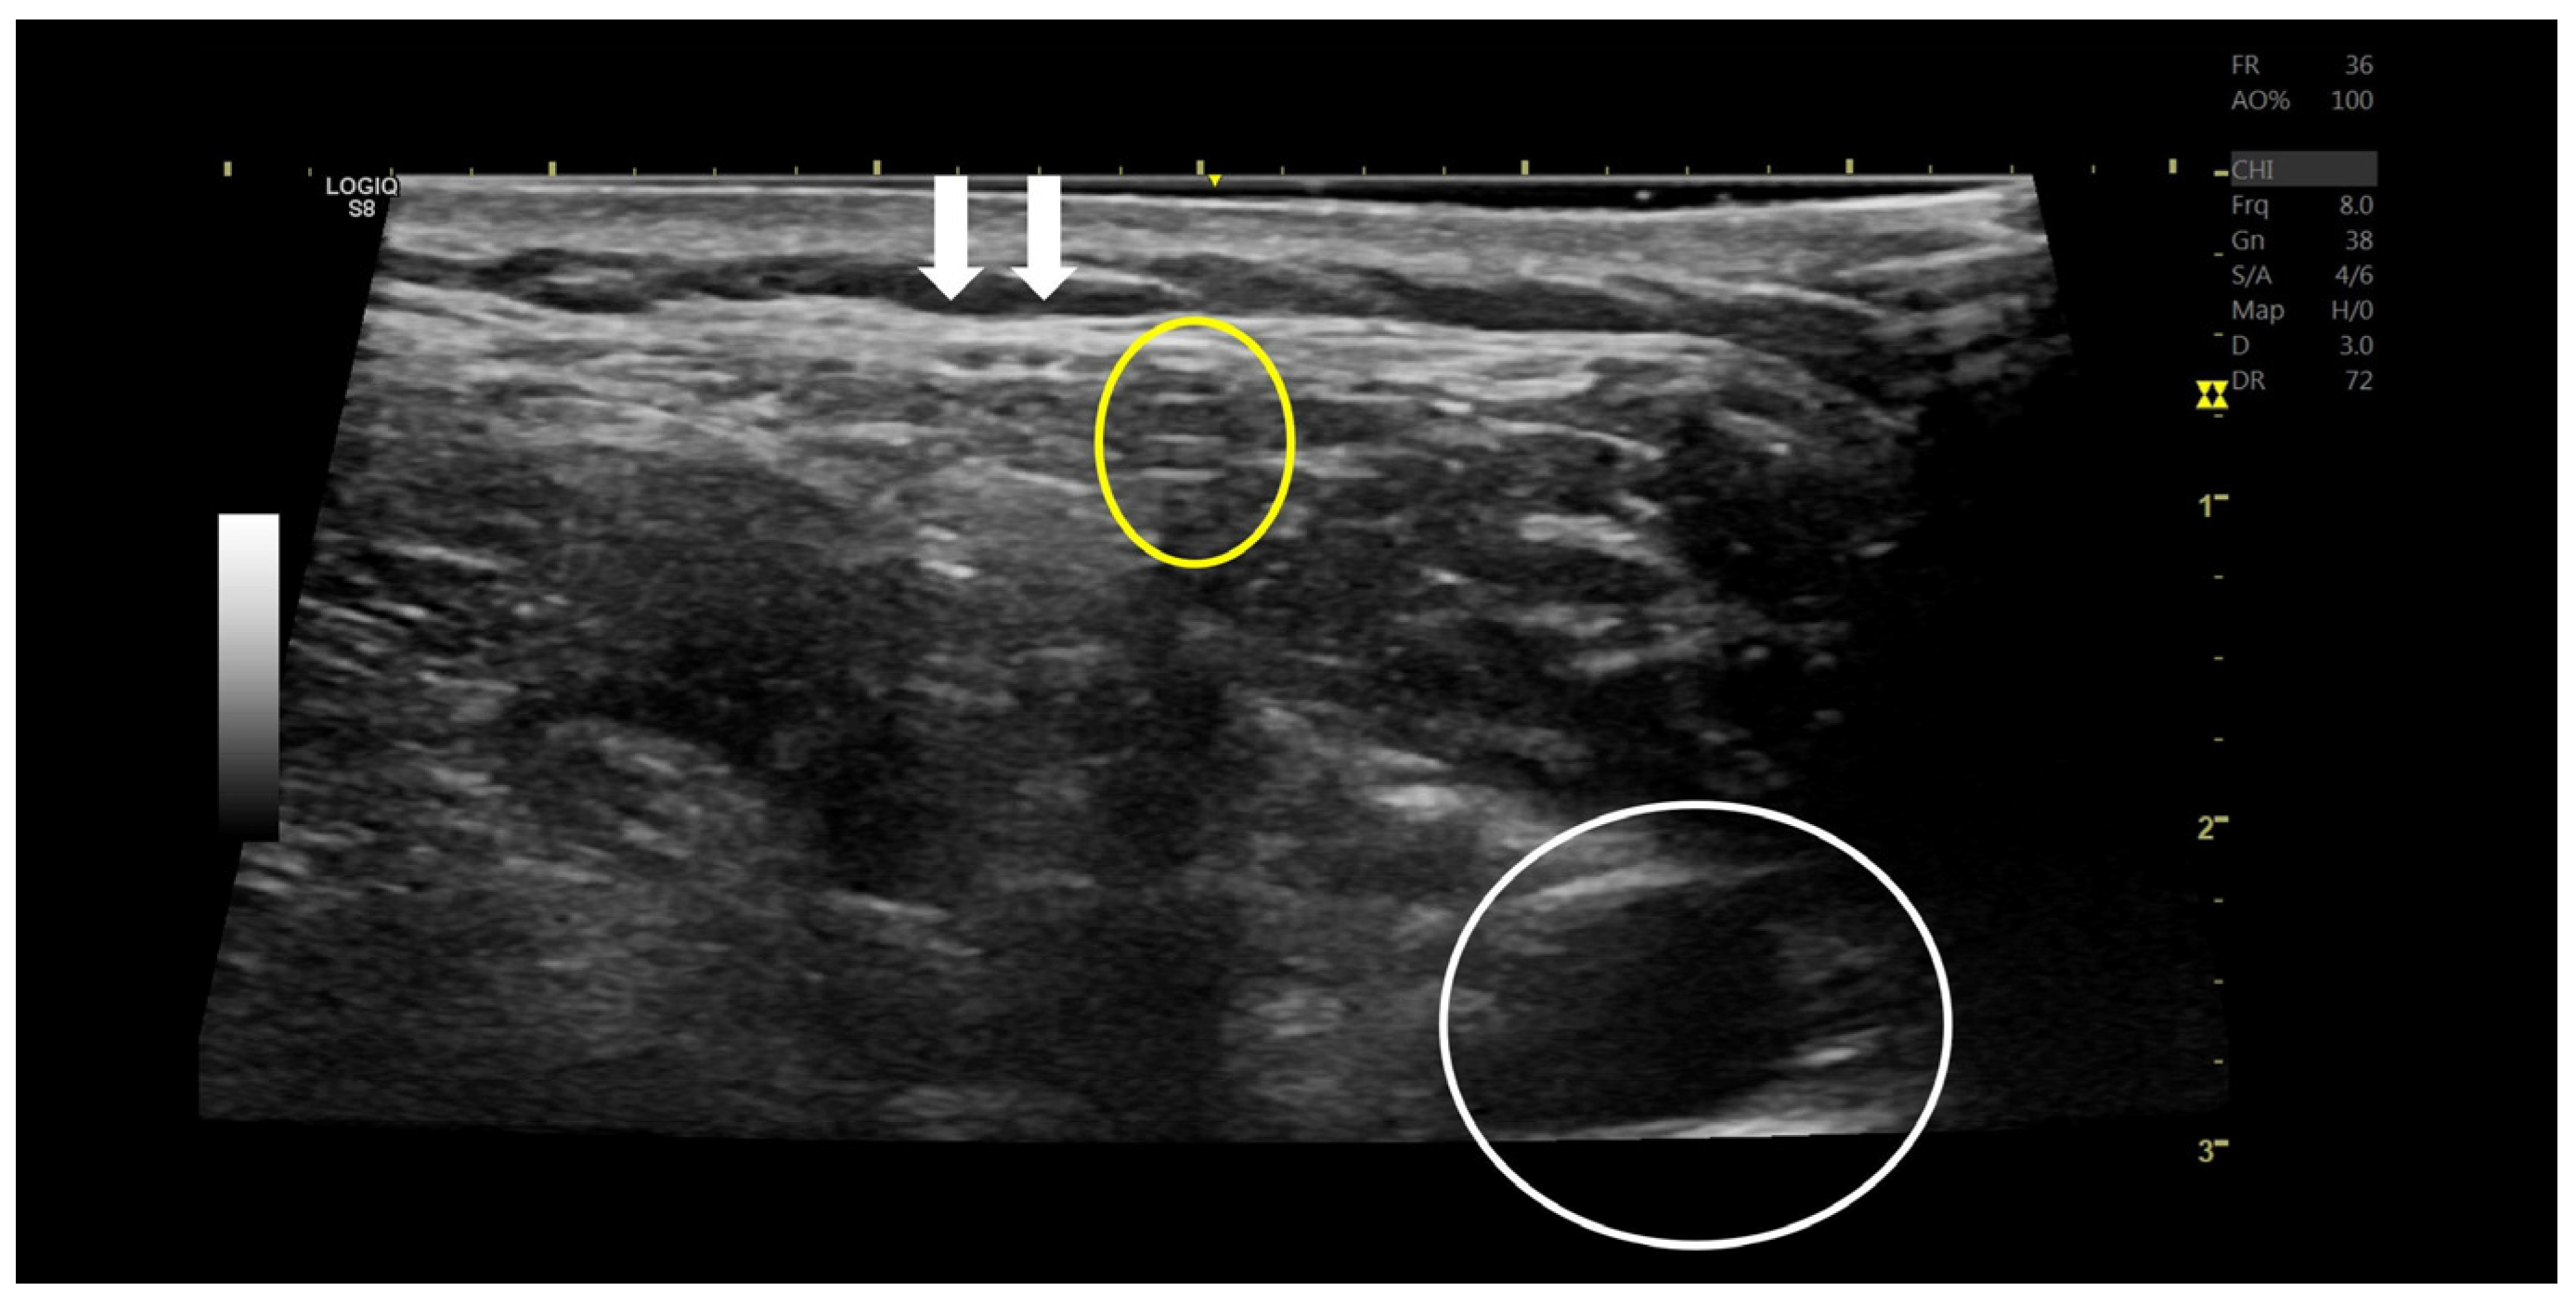

2. Case Description